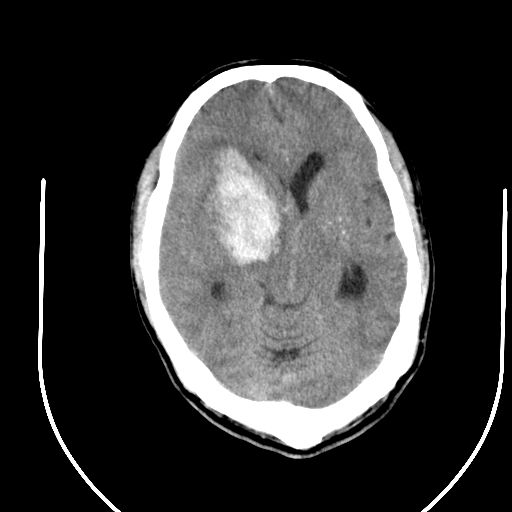

标题: CT24997:M,60Y,突发昏迷30分钟,有高血压病史。 [打印本页]

标题: CT24997:M,60Y,突发昏迷30分钟,有高血压病史。

右侧基底节区脑出血并破溃入脑室。

支持楼主诊断,脑中线结构有偏移,脑疝形成可能!

1右侧基底节脑出血伴脑干出血并破入脑室系统脑疝形成2梗阻性脑积水

1)右侧基底节脑出血伴脑干出血并破入脑室系统。2)大脑镰下疝。3)梗阻性脑积水。

1、右侧基底节脑出血伴脑干出血并破入脑室系统。

2、大脑镰下疝。

3、梗阻性脑积水。